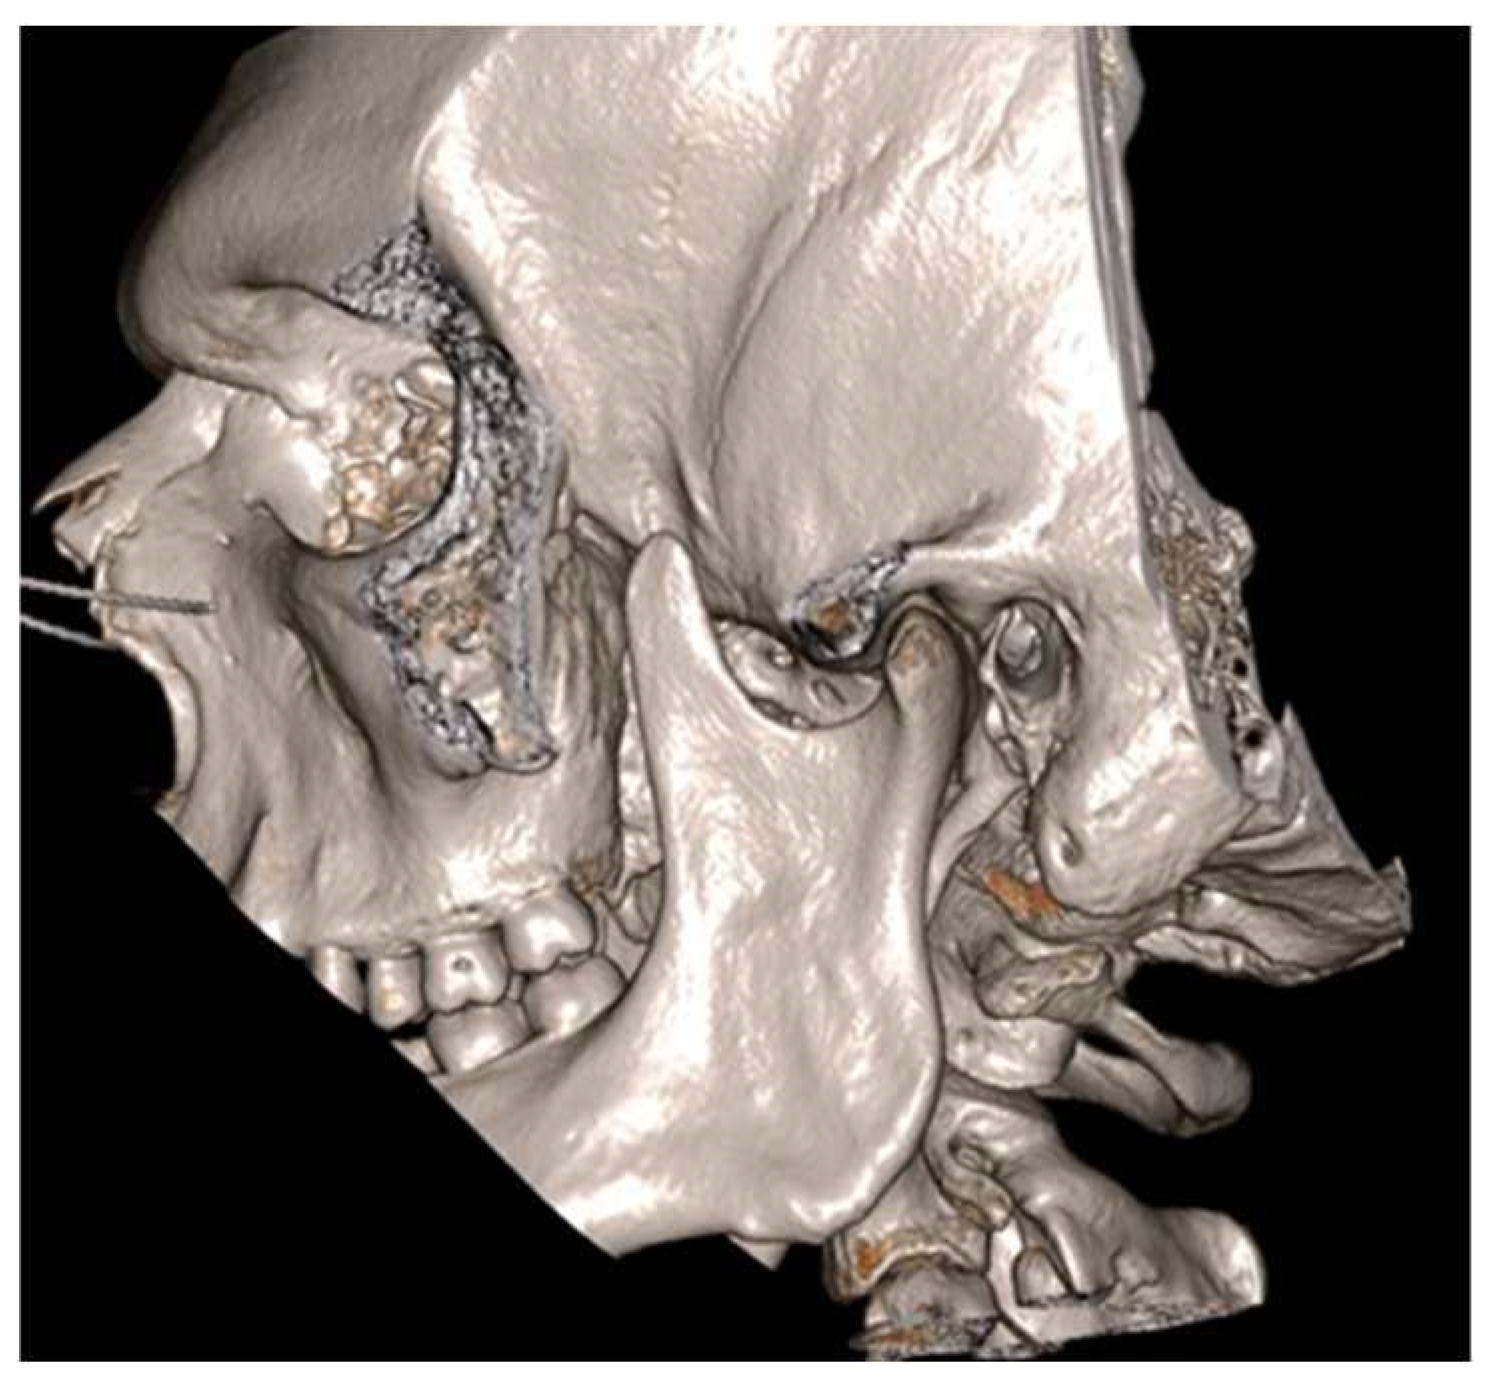

Figure 2.

Cinematic 3D reconstruction (Mimics, Materialise NV, Leuven, Belgium) showing the pseudojoint established between the altered right CPM and the inner aspect of zygomatic bone.

A 19-year-old woman was referred to us, presenting with a history of progressive limitation in mouth opening over the previous 18 months. She complained of a dull pain just in front of her right ear, exacerbated by palpation and mandibular movements. She had no medical history and did not report any previous local trauma. She was initially diagnosed with temporomandibular disease (TMD) dysfunction and treated conservatively with an occlusal bite with no symptomatologic relief. At physical examination, the maximum mouth opening (MMO) was reduced to 25 mm, but mandibular movements were preserved. No articular noises during temporomandibular joint (TMJ) bilateral palpation were perceived, but she complained of pain in the masticatory muscles bilaterally. No malocclusion, facial asymmetry or swelling were identified. The orthopantomogram (OPG) (Figure 1) and the magnetic resonance imaging (MRI) were negative. Given the absence of clinical improvement but a rather slow and progressive reduction in MMO, a computed tomography (CT) was performed, revealing an enlargement and an abnormally shaped right CPM, establishing a close relationship with the zygomatic arch (Figure 2). Furthermore, single-photon emission computed tomography (SPECT) was prescribed, and the late images of bone uptake showed a focal increase in the correspondence of the so-called pseudojoint between the jaw and the right zygomatic bone compared to the left side (Figure 3). According to this, a provisional diagnosis of JD was made. The patient underwent a right coronoidectomy through an intraoral approach under general anesthesia with awake, blind, nasal intubation. The right, mushroom-shaped coronoid process was identified and resected, and a sort of fibrotic capsule between the inner aspect of the zygoma and the CPM was highlighted, establishing the pseudojoint, with this confirming the diagnosis of JD (Figure 4). Histopathologically, the specimen showed a growth pattern of hyperplastic bone tissue covered by cartilaginous layers and an external coating of dense fibrous tissue. There were no intra-operative or immediate postoperative complications. Postoperative CT was obtained for baseline follow-up. The MMO increased to about 30 mm in the immediate postoperative period, and this improved to 40 mm after a month of aggressive physiotherapy. She underwent clinical and radiological follow-up, and after 12 months, the MMO was stable, and no recurrence was observed.